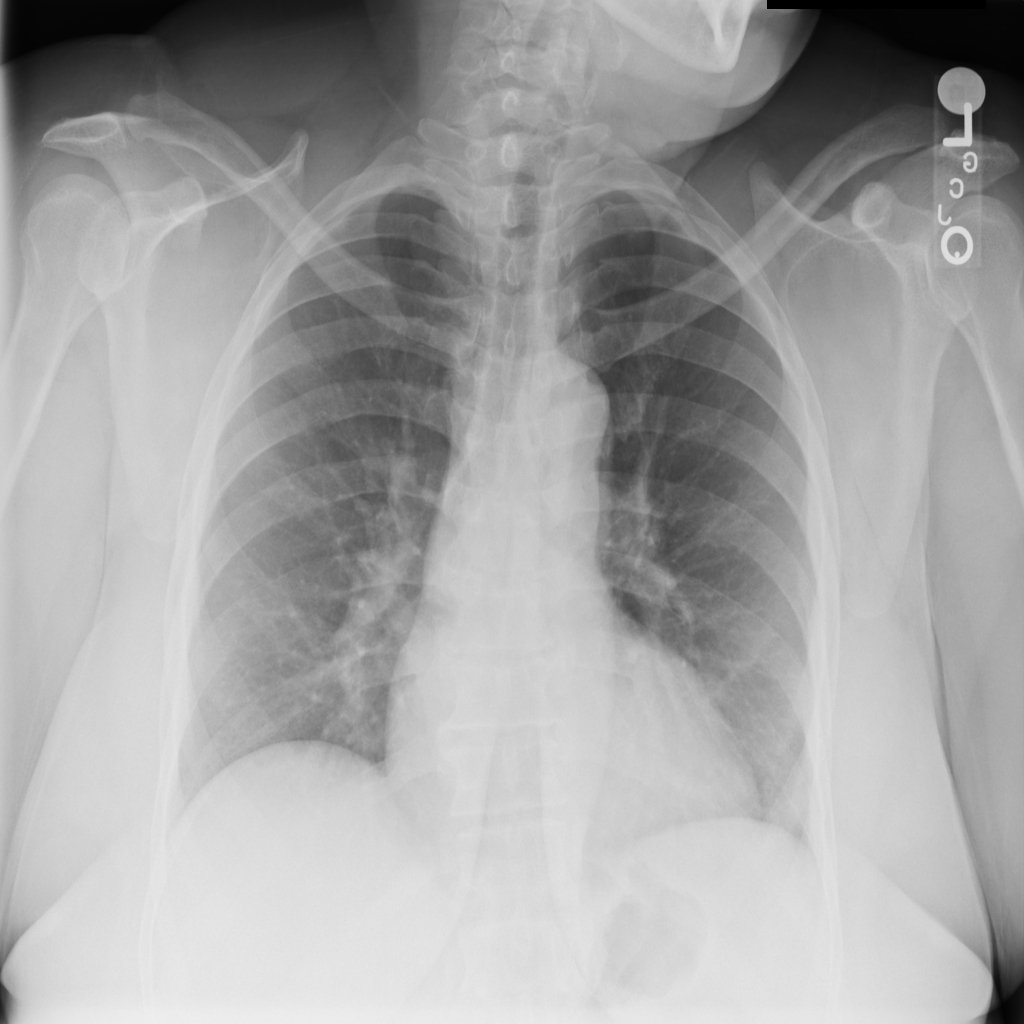

Cardiomegaly

Cardiomegaly means the heart appears enlarged on the chest X-ray. It is a descriptive imaging finding that can be related to heart strain, chronic pressure or volume changes, or even projection effects.

Showing up to 90 reference images for Cardiomegaly.

PAT-3384 · IMG-000Cardiomegaly

PAT-3384 · IMG-000

AP